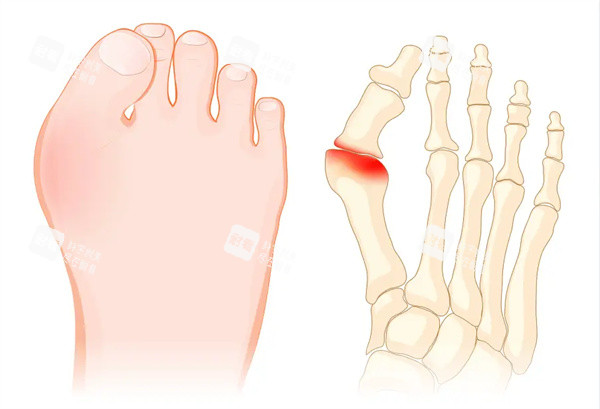

“哎哟喂!这大脚骨一走路就钻心疼,高跟鞋不敢穿,运动鞋磨得慌,连跳广场舞都成了奢望!”北京朝阳区的刘阿姨捂着脚直叹气,她这拇外翻的毛病折腾了五年,试过矫正器、贴膏药,然后还是决定找医生手术。可一打听,苏敬达和马桂文两位医生都挺有名,一个骨科博士,一个27年老医生,选谁?这问题就像“豆腐脑吃甜还是咸”,可把人愁坏了!

更出色的是,他还搞了个“医学美足标准”,把矫正和美学结合,术后脚型自然不臃肿。有患者说:“马医生手术精细得像绣花,术后肿胀轻,改善比较快,连鞋垫都不用定制!”

总结:选医生就像选对象,没有肯定的好坏,只有合不合适!苏敬达适合职场人、爱美人士;马桂文适合重度畸形、追求高端服务的患者。